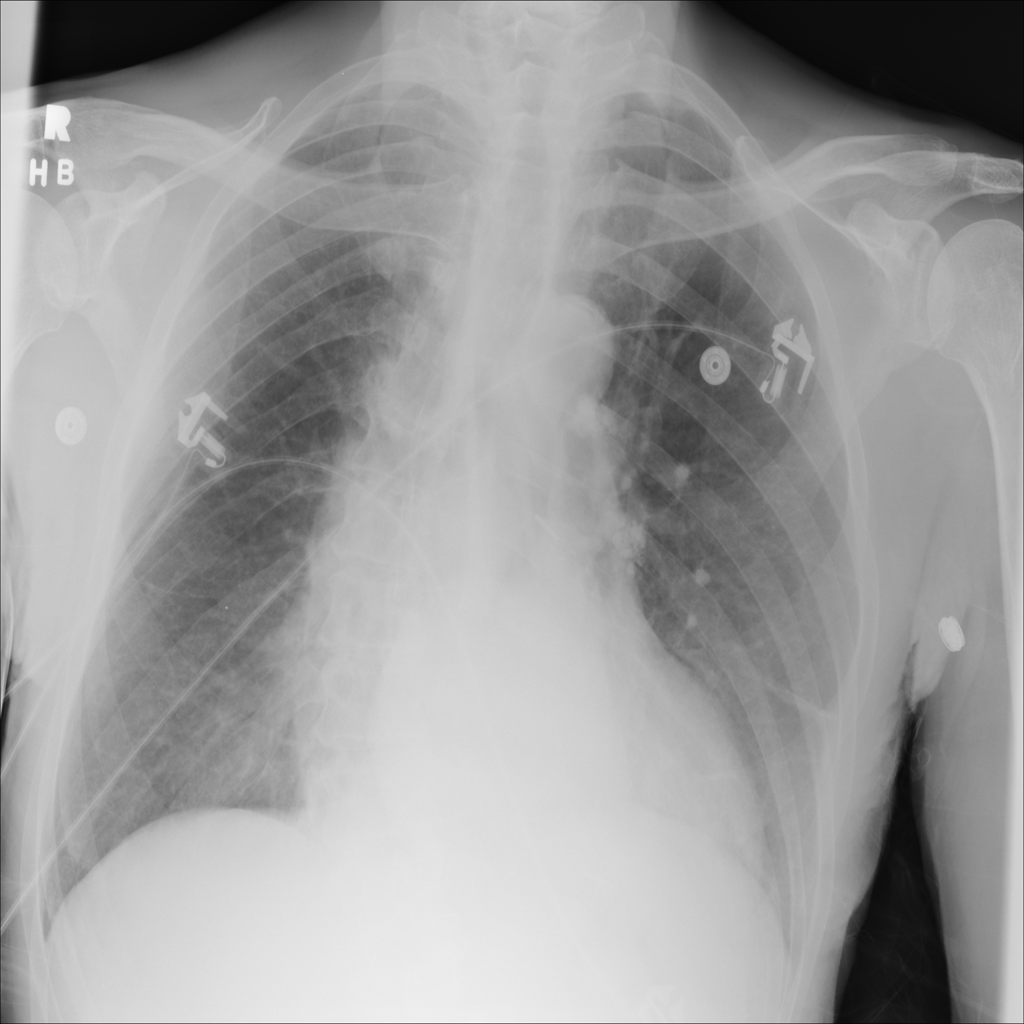

PAT-4F7E · IMG-000Hernia

PAT-4F7E · IMG-000

PA